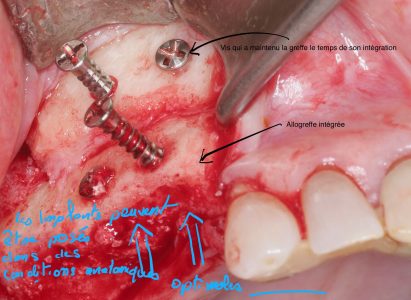

Les photos qui illustrent le texte ont pour unique objectif de vous aider à mieux comprendre les techniques utilisées. Elles correspondent chacune à une réalité qui ne peut être transposée car chaque situation clinique est différente et unique.

L’intervention chirurgicale consiste en une reconstruction osseuse du maxillaire ou de la mandibule avant la mise en place des implants dentaires par votre chirurgien.